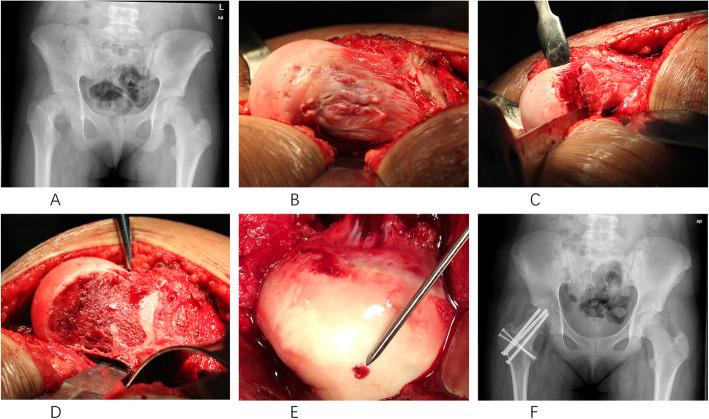

We retrospectively assessed the outcomes of all twenty patients who had been treated with the modified Dunn procedure in our tertiary-care institution. According to the Loder and Fahey criteria, all cases were classified as severe slips; nineteen cases were stable, and one case was an unstable slip. All surgical procedures were performed by one senior orthopedic surgeon who had specific training in the modified Dunn procedure. Operative reports, outpatient records, follow-up radiographs, and the intraoperative findings were reviewed to determine the demographic information, type of fixation, final slip angle, presence of avascular necrosis (AVN), and any additional complications. The mean age of the patients was 13.2 ± 1.6 years (range, 10 to 17 years). Twenty patients (twenty-one hips) with a mean of 31.2 ± 14 months (range, 12 to 57 months) follow-up met the inclusion criteria. Pain and function were assessed by the modified Harris score and WOMAC score. Radiographic anatomy was measured using the slip angle and α-angle. The radiographic findings related to the anatomy of the femoral head-neck junction, as well as signs of early-onset of osteoarthritis (OA) and AVN, were evaluated pre- and postoperatively.

RESULTS

Overall, nineteen patients had excellent clinical and radiographic outcomes with respect to hip function and radiographic parameters. One patient (5%) who developed implant failure at 3 months postoperatively had a poor outcome. The mean preoperative slip angle was corrected from 63.2 ± 8.1° (range, 51 to 84°) to a normal value of 7.5 ± 3.5° (range, 2 to 15°) (p < 0.01). The mean α-angle was improved from an average of 94.5 ± 21.1° (range, 61 to 123°) to postoperative 42 ± 6.4° (range, 25 to 55°) (p < 0.01). The mean modified Harris hip and WOMAC scores postoperatively were 96.7 ± 13.4 (range, 40 to 100) and 95.4 ± 10.6 (range, 38 to 100), respectively. There were no cases of the development of femoroacetabular impingement (FAI) and the progression of OA. We did not record any case of AVN, closure of the growth plate, heterotopic ossification (HO), trochanteric nonunion, or limb length discrepancy that occurred postoperatively either at the most recent follow-up.